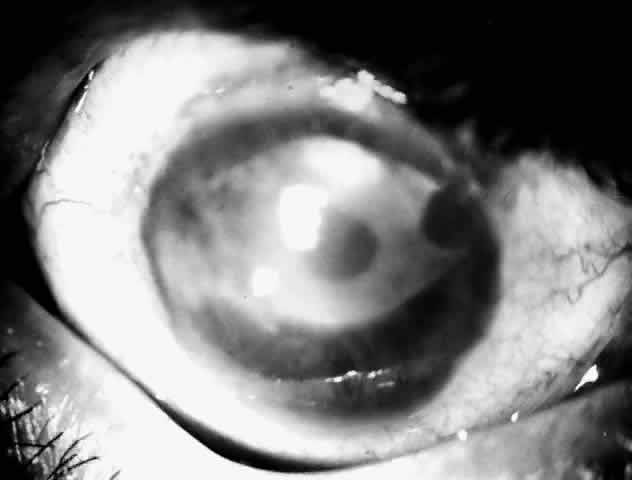

Bacterial corneal infections are caused by a wide variety of organisms. Pneumococcus seems to be the most common causative organism (Fig. 2); however, staphylococcal, pseudomonal, and gonococcal infections frequently are encountered.3 This may be related to chronic dacryocystitis.5

Fig. 2. Photograph demonstrating a pneumococcal corneal ulcer.